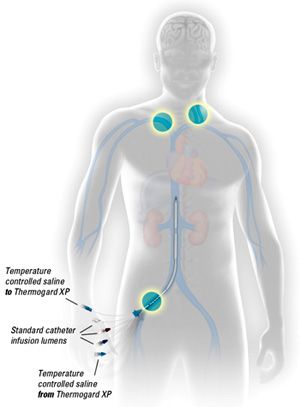

Přístroj Coolgard – tato endovaskulární metoda využívající speciální katetr, který je zaveden do dolní duté žíly cestou vény femoralis, je velmi efektivní. V uzavřeném okruhu proudí chladný fyziologický roztok, jehož teplota a rychlost cirkulace jsou řízeny extrakorporální jednotkou, která vyhodnocuje informace na základě teploty tělesného jádra. Tato teplota je měřena z teplotního čidla napojeného na speciální permanentní močový katetr (PMK). Způsob zavedení je totožný se zaváděním centrálního žilního katetru (CŽK), nezbytností je použití sterilního stolku a aseptický přístup jak ze strany lékaře, tak i ze strany všeobecné sestry. Tento speciální katetr je trojcestným CŽK, který má ovšem další vstup a výstup pro uzavřený okruh cirkulace chladicího média (fyziologický roztok 1/1; FR). Tento FR protéká v balóncích podél katetru, a tak dochází k tepelné výměně mezi chladným roztokem a krví.

Intranazální systém ochlazování

Zdroj: Fotoarchiv firmy Benechill (http://www.puro-klima.cz)

Katetr zavedený do v. femoralis

Zdroj: Fotoarchiv firmy Medial, 2009